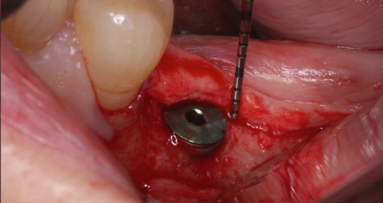

Following a thorough evaluation, an autogenous connective tissue graft was placed subepithelially to achieve a symmetrical look in one surgical procedure. After anesthetizing the patient, the flap outline and its reflection toward the labial were completed (Figs. 5, 6). The connective tissue donor site could have been selected from various areas. In this particular case, the tuberosity area was used. The donor tissue was de-epithelialized, and the deformed edentulous area was sculpted to the desired shape. The original flap outline was designed to prevent recession on the adjacent teeth and to provide a covering for the graft to avoid a keloid on the crest. During healing, a keloid would have been a different color, which would have detracted from the goal of harmonious color integration. The flap outline was then extended palatally to include more attached gingival, which avoided a keloid and retained the graft. When the autogenous free connective tissue graft was in the desired location (Fig. 7), the flap was repositioned and sutured for stability.